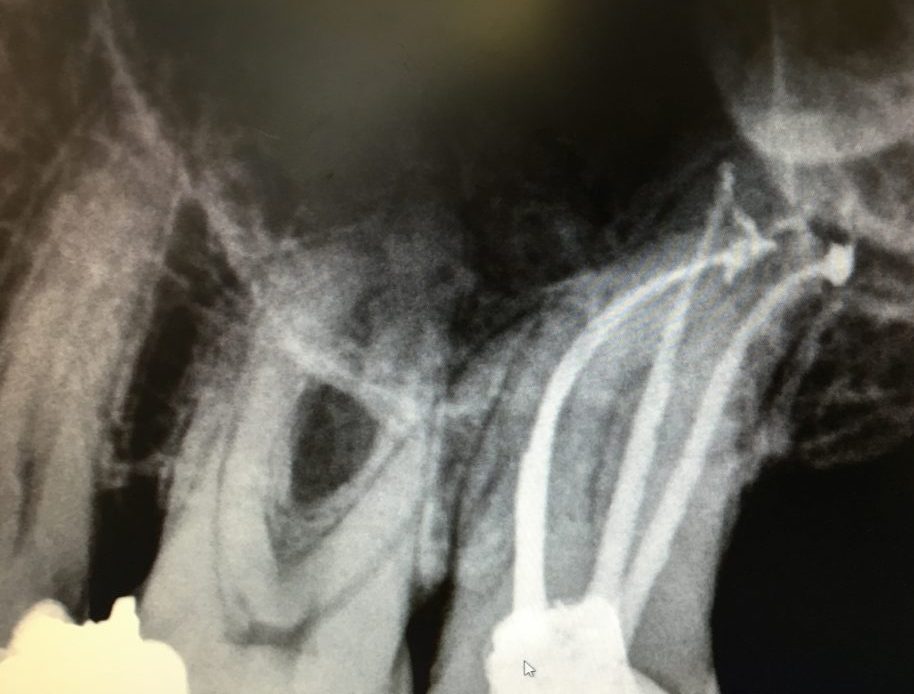

Before root canal treatment at Rajarhat Dental Hall After root canal treatment with visibly repaired teeth at Rajarhat Dental Hall

1. Diagnosis & X-ray – A dental check up is done to confirm infection using digital X-rays.